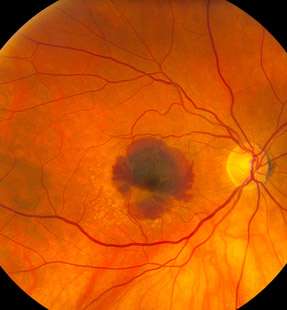

What Is Age-Related Macular Degeneration(AMD)?

AMD is a common eye condition and a leading cause of vision loss among people age 50 and older. It causes damage to the macula, a tiny area near the center of the retina and the part of the eye responsible for sharp, central vision, which is straight ahead. In some people, AMD advances so slowly that vision loss does not occur for a long time. In others, the disease progresses quickly and may lead to a loss of vision in one or both eyes. As AMD progresses, a blurred area near the center of vision is a common symptom. Over time, the blurred area may grow larger or you may develop blank spots in your central vision.

In neovascular AMD, also called WET AMD, abnormal blood vessels grow underneath the retina. These vessels can leak fluid and blood, which may lead to swelling and damage of the macula. The damage may be rapid and severe, unlike the more gradual course of Dry AMD. It is possible to have both DRY and WET AMD in the same eye, and either condition can appear first.